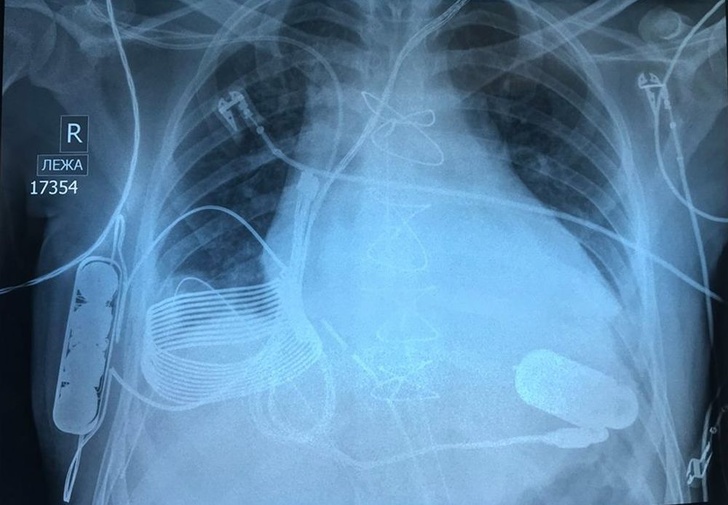

13. Рентгенівський знімок грудної клітки, в яку впровадили бионическое серце з можливістю бездротової зарядки